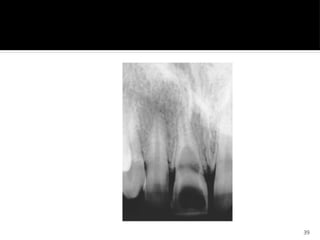

Pulp calcifications

Masses of calcified tissue present on pulp

chamber and roots of teeth

Common phenomenon occurs with increasing

age

Classified

1. Based on morphologic forms

- Discrete pulp stones

- Diffuse calcifications